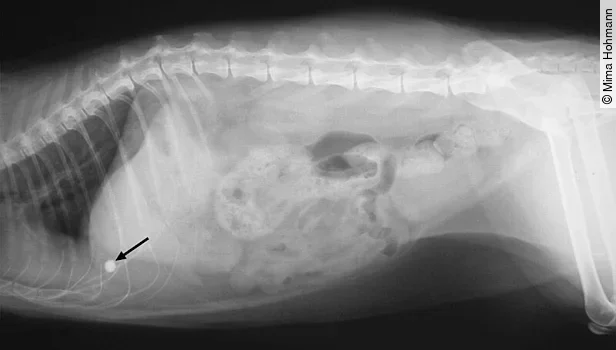

Blasenbeschwerden

Auch bei Blasenschmerzen durch eine chronische Zystitis, Kristalle (Struvit- oder Oxalatkristalle [[Abb. 6]]) oder Blasensteine ([Abb. 7]) leckt sich die Katze das Abdomen. Ist der Blasen- oder Nierenbereich druck- und/oder schmerzempfindlich, sollte man eine Harnuntersuchung durchführen, ggf. auch einen abdominalen Ultraschall.

Nierensteine ([Abb. 8]) kommen bei der Katze nicht so häufig vor, müssen aber auch in Betracht gezogen werden, da auch sie ausstrahlende Schmerzen verursachen.